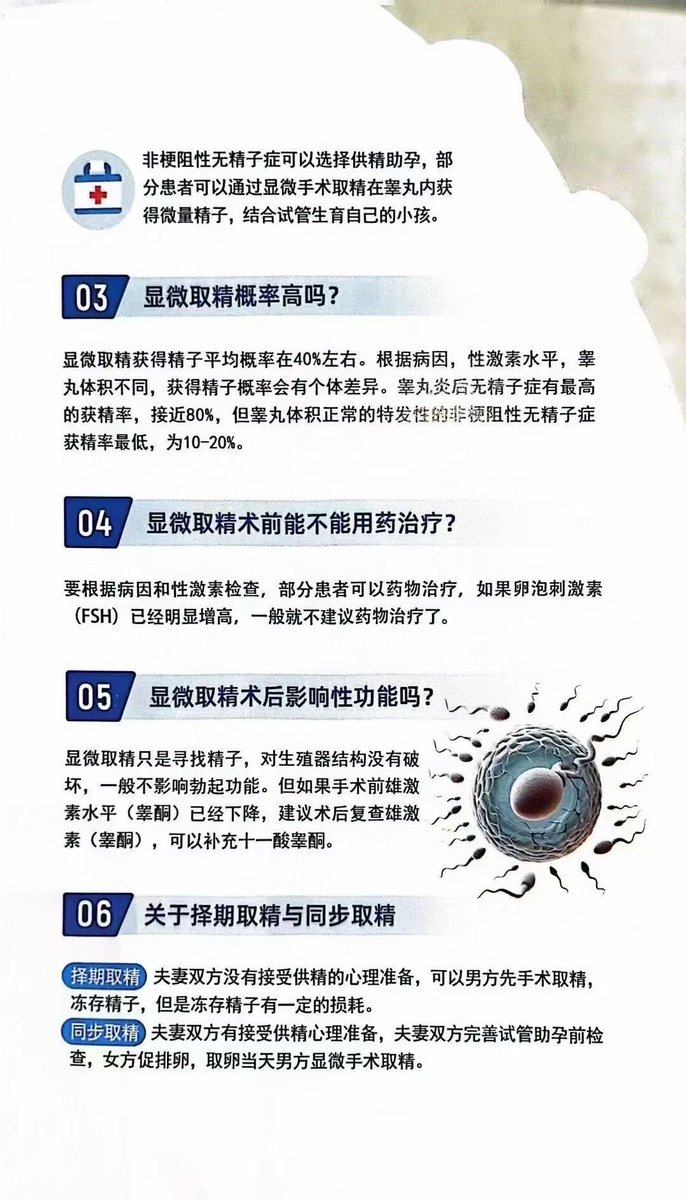

![代孕.HIV.洗精.国内代孕机构 (@wangjb168) on Twitter photo 【等待篇】

单胎11周 复查结果正常[庆祝]

专业试管代孕咨询微信:a18025307951

#HIV生子 #三代代孕 #失独代孕 #二代代孕 #包成功代孕 #洗精代孕 #三代包成功 #选性别代孕 #女性代孕 #男性代孕 #夫妻代孕

#试管婴儿 #试管助孕 #代孕 #广州代孕 【等待篇】

单胎11周 复查结果正常[庆祝]

专业试管代孕咨询微信:a18025307951

#HIV生子 #三代代孕 #失独代孕 #二代代孕 #包成功代孕 #洗精代孕 #三代包成功 #选性别代孕 #女性代孕 #男性代孕 #夫妻代孕

#试管婴儿 #试管助孕 #代孕 #广州代孕](https://pbs.twimg.com/media/GyI_LRiaEAIT3EI.jpg)